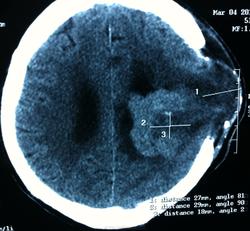

КТ контроль после операции.

Мне видится так. Иначе в данной локализации просто неоткуда расти оболочечной опухоли. На контрольной КТ, после декомпрессии, когда срединные структуры стали действительно срединны, правое обызвествленное сосудистое сплетение видно отчетливо, а левое, где оно? Ведь если бы образование компремировало, то после операции, когда часть мозга пролабировало в трепанационное отверстие мы бы увидели и левое сосудистое сплетение, но оно интимно связано с образованием и даже "потянулось" за ним в сторону декомпрессионного отверстия, потому что это и есть "росток" откуда выросла опухоль.